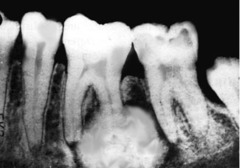

periapical granuloma

Front

-asymptomatic, tooth sensitive to percussion, slight extrusion of tooth -radiographically: slight thickening PDL and periodontal radiolucency CHRONIC